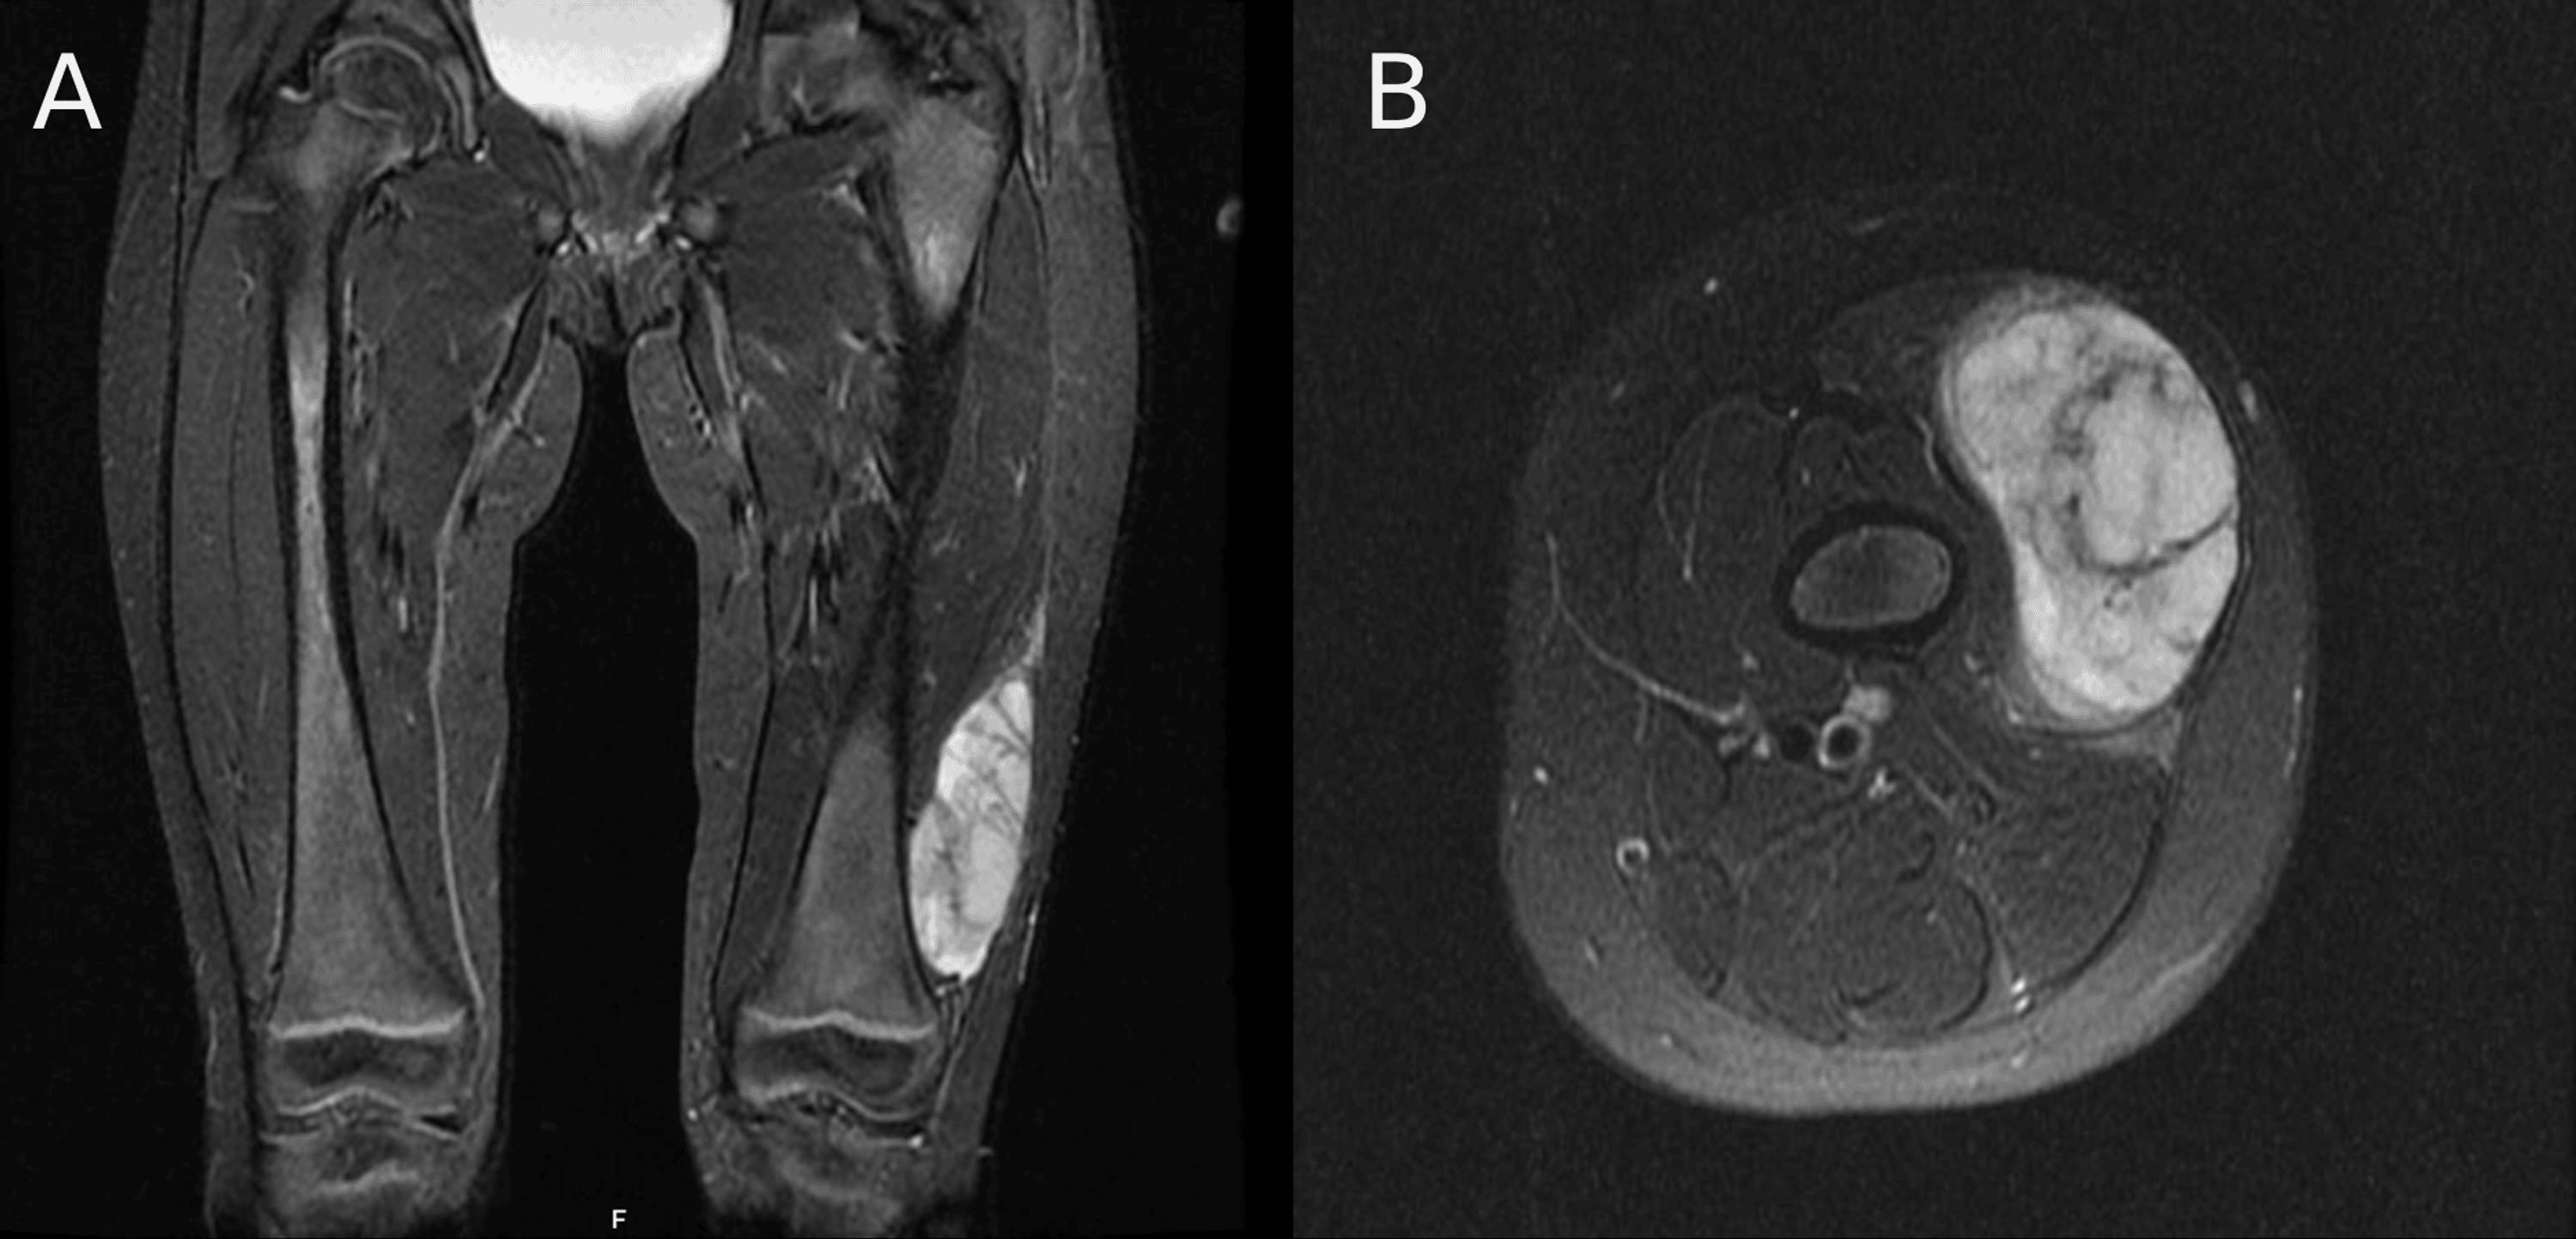

From tumorsurgery.org

Page Management Spindle Cell Fibrosarcoma What is spindle cell sarcoma? A spindle cell sarcoma is a soft tissue tumor that originates in a bone. Spindle cell sarcoma is a rare form of bone cancer or soft tissue cancer. Spindle cell sarcoma is an extremely rare bone cancer. Spindle cell tumor and spindle cell sarcoma are descriptive names used when tumor cells look long and narrow. Spindle Cell Fibrosarcoma.

Page Management Spindle Cell Fibrosarcoma A spindle cell sarcoma is a soft tissue tumor that originates in a bone. What is spindle cell sarcoma? Spindle cell sarcoma is a rare form of bone cancer or soft tissue cancer. Spindle cell tumor and spindle cell sarcoma are descriptive names used when tumor cells look long and narrow under the microscope. Spindle cell sarcoma is an extremely. Spindle Cell Fibrosarcoma.